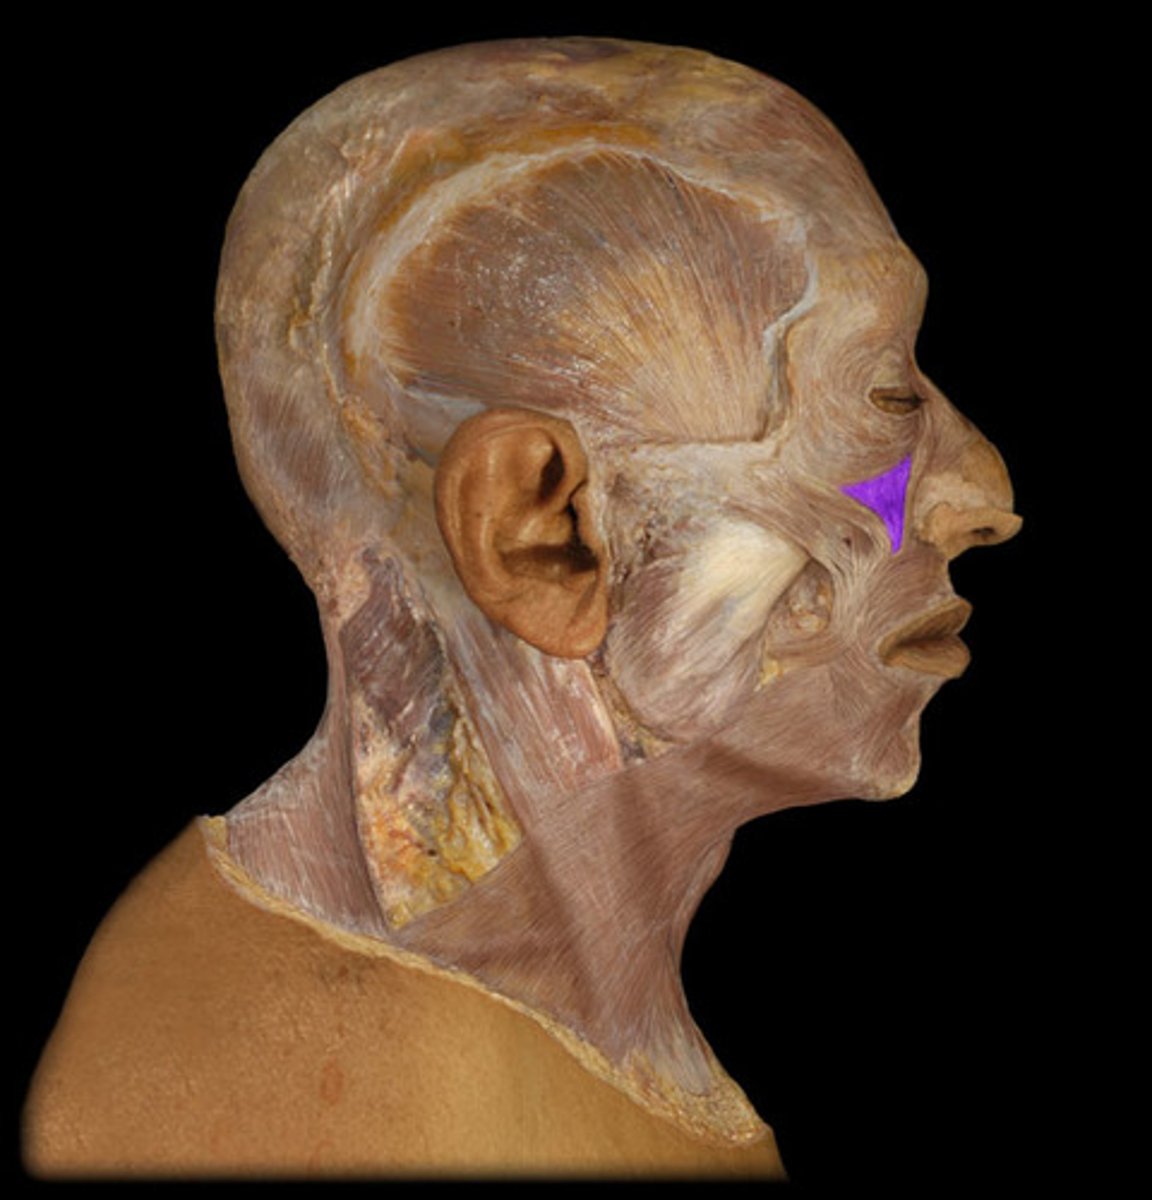

Medial pterygoid